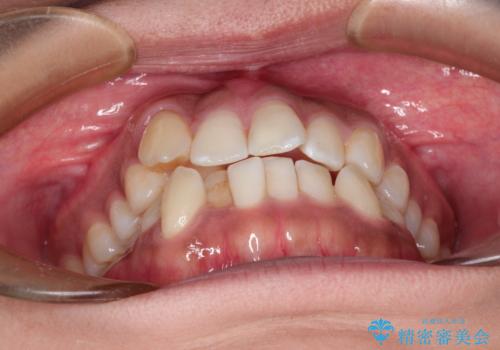

インビザラインと補助装置の併用による八重歯の抜歯矯正

- 八重歯を治したいとのことで来院されました。

重なりが強い右側の上下の歯を1本ずつ抜歯する計画としました。

インビザラインでの治療がご希望でしたが、右上の歯のかさなりが強いところは、補助装置である程度動かしてからインビザラインに移行することにしました。

下顎はインビザラインのみで治療を行いました。